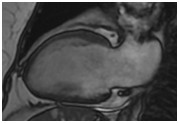

正常心肌